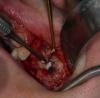

CSS Опубликовано 26 декабря, 2012 Поделиться Опубликовано 26 декабря, 2012 Уважаемые коллеги, очередной экспериментальный синус с использованием аллогенов!!! Ждемс результатов!!!P.S. И естественно жду Ваших коммментов и замечаний!!! ;-))) 4 Ссылка на комментарий

CSS Опубликовано 26 декабря, 2012 Автор Поделиться Опубликовано 26 декабря, 2012 спасибо, хорошие фотки. А почему эксперимент?Такое впечатление по ОПТГ после синусов, что в 1 сегменте графт пополз скврзь мембрану, как бы нет уровня имхоСпасибо за кейс.Эксперимент с Алло, это немецкий материал, смесь кортикальной и губчатой кости. Использовал впервые. Относительно проползания графта, там очень сложная анатомия была, за 3 мес до этого было удаление с перфами. Слизистая утолщена, и отслоена целой. Рентген - это доп метод!!! ;-))) Под слизистой Prp и Алло мембрана из фасции!!! Ссылка на комментарий

CSS Опубликовано 26 декабря, 2012 Автор Поделиться Опубликовано 26 декабря, 2012 чем отслаивали окно в синус от мембраны?какой алло материал использовали? И пропилы и отслойка, пьезо, далее кюретами. Тут Даск. Про Алло, материал Остеографт, пока не зарегиный в РФ, смесь кортикалки и губки!!! Производят немцы. Ассортимент масштабный, есть и комбинирированные гиалуронкой и деминерализированные, но я хочу сам разобраться, что лучше и интереснее для меня. Цена реально смешная, по сравнению с синтетиками и ксенографтами. Ждемс результатов. Через 4 мес контр КТ и решим, что там выросло, а то мож на эндоскопическую санацию синуса прийдется пацика посылать!!!! ;-)))))) Ссылка на комментарий

CSS Опубликовано 26 декабря, 2012 Автор Поделиться Опубликовано 26 декабря, 2012 по вашему кейсы - импланты углубил бытакое впечатление что в области 25 не хватает графтаокно сделал бы меньше (есть же даск). ваш кусок может секвестрироватьсянужно стандартизировать фотопротокол а так все норм. спасибо за кейсработаю алло почти 2 годавсе нравится и ничего там не нагнаивается - для доктора шу Спасибо за комментарий, но окно намеренно делалось таким, ввиду сложной анатомии в зоне 26 и 27. У меня есть Даск, и очень прикольный набор, но лично по мне не всегда применим, ввиду длинной ножки бора, об этом мы еще пополимеризуем на конгрессе в Краснодаре!!!!!! ;-)))) В зоне 25 все ок!!! Просто этот граф не всегда контрастен. А деминерализованный алло вообще не виден после операции, и бывало ощущение, что винты в воздухе, но контрольное кт, развеяло сомнения!!! ;-)))Относительно углубления, если б это был Дентиум, то углубил бы на 0,5, но тут Горизонт, о своих наблюдениях уже писал выше!!!Насчет фотопротокола, ну не всем так везет, иметь штатных профессиональных фотографов, так что не обессутьте!!! ;-))) А как у Вас с аллоблоками??? Каков протокол??? Вымачиваете??? Какую толщину ламината используете??? Ссылка на комментарий